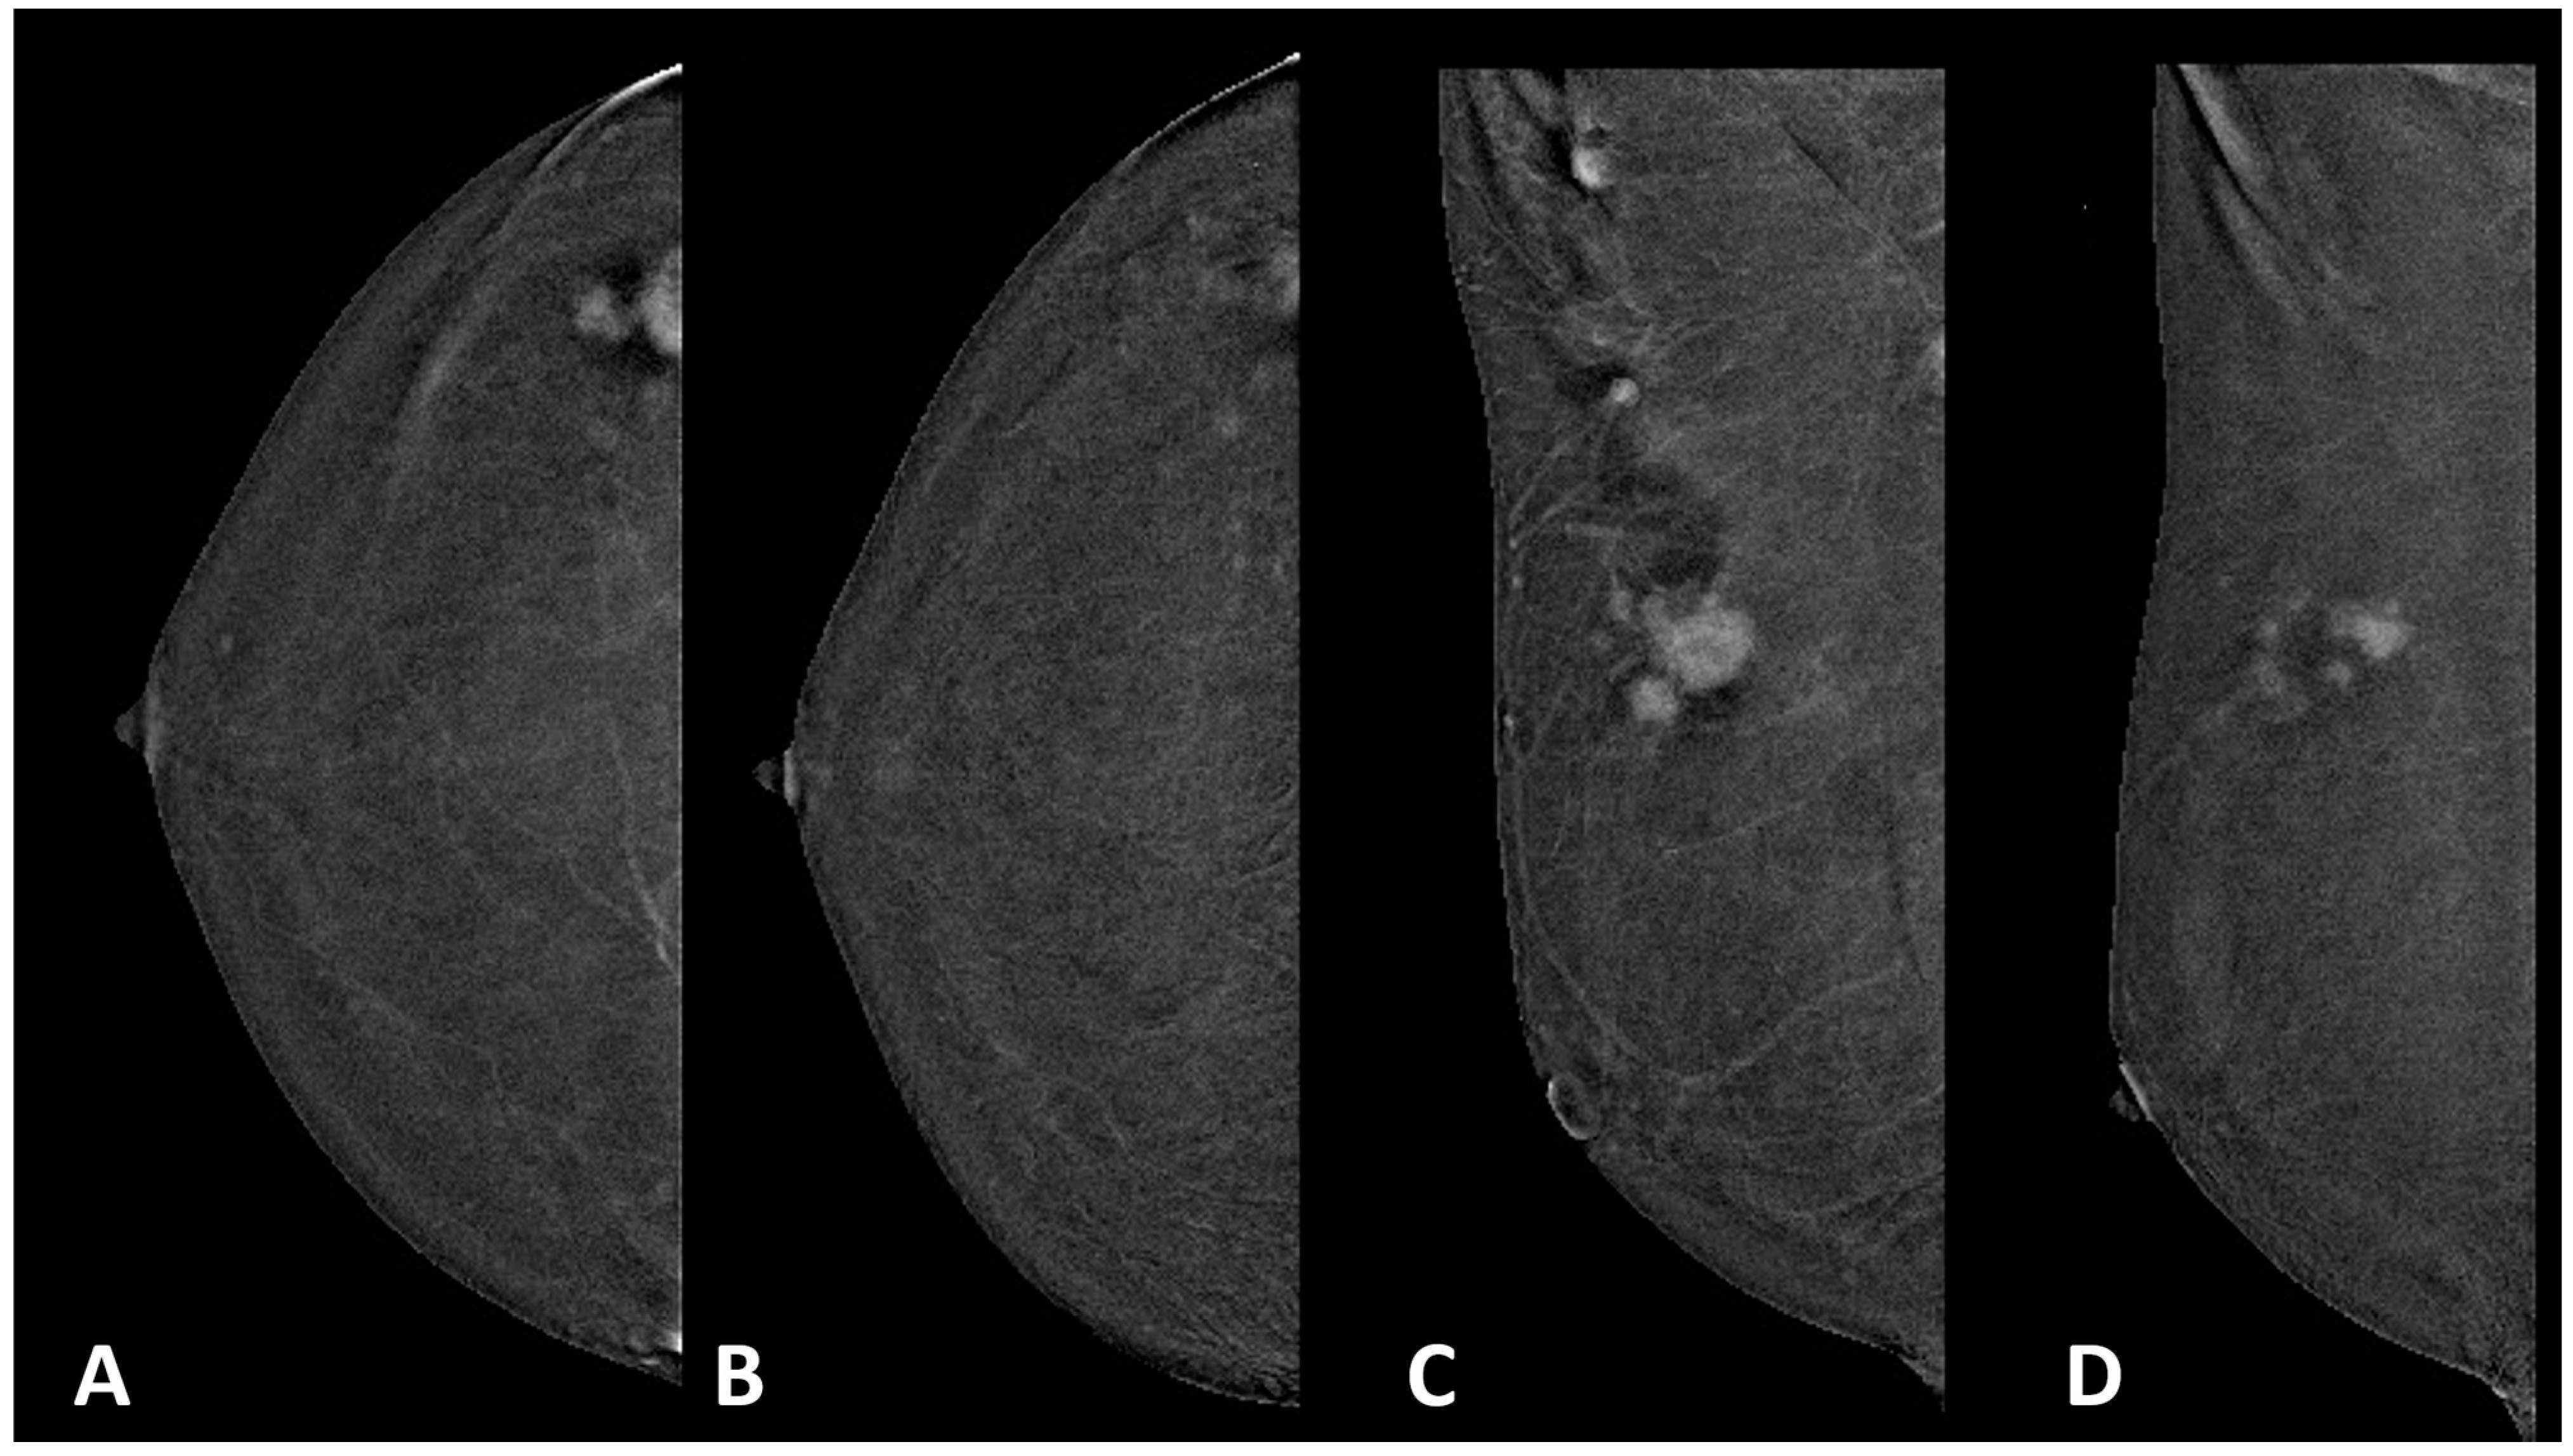

Simple Summary

2. Materials and Methods

2.1. CEM Examination

2.2. Image Analysis